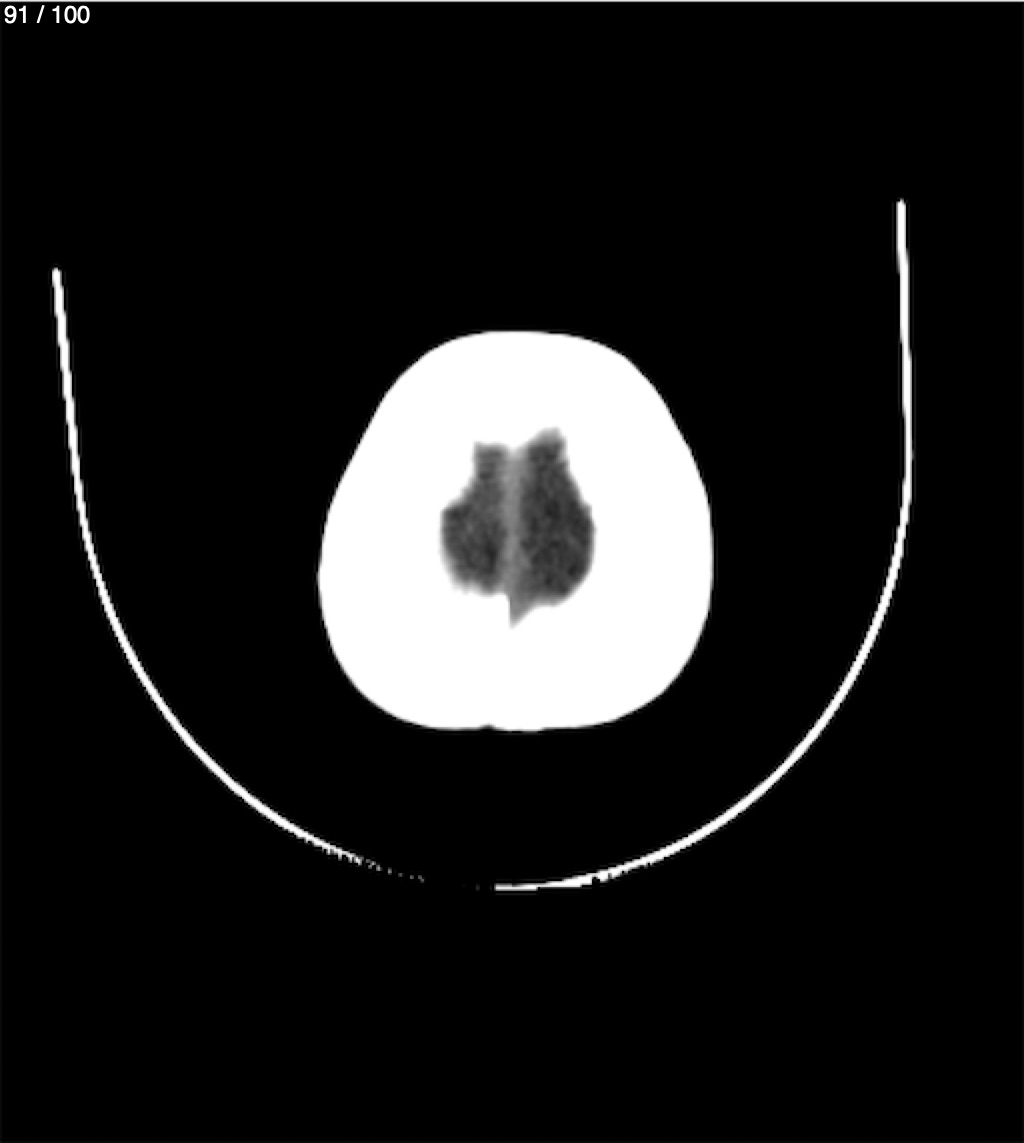

Catarino Perez Escobar 85A - T.C Craneo